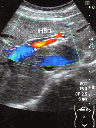

肝内胆管拡張

心窩部横走査